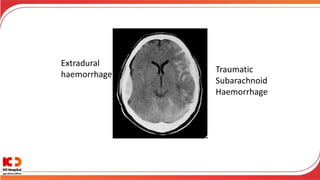

Extradural

haemorrhage

Traumatic

Subarachnoid